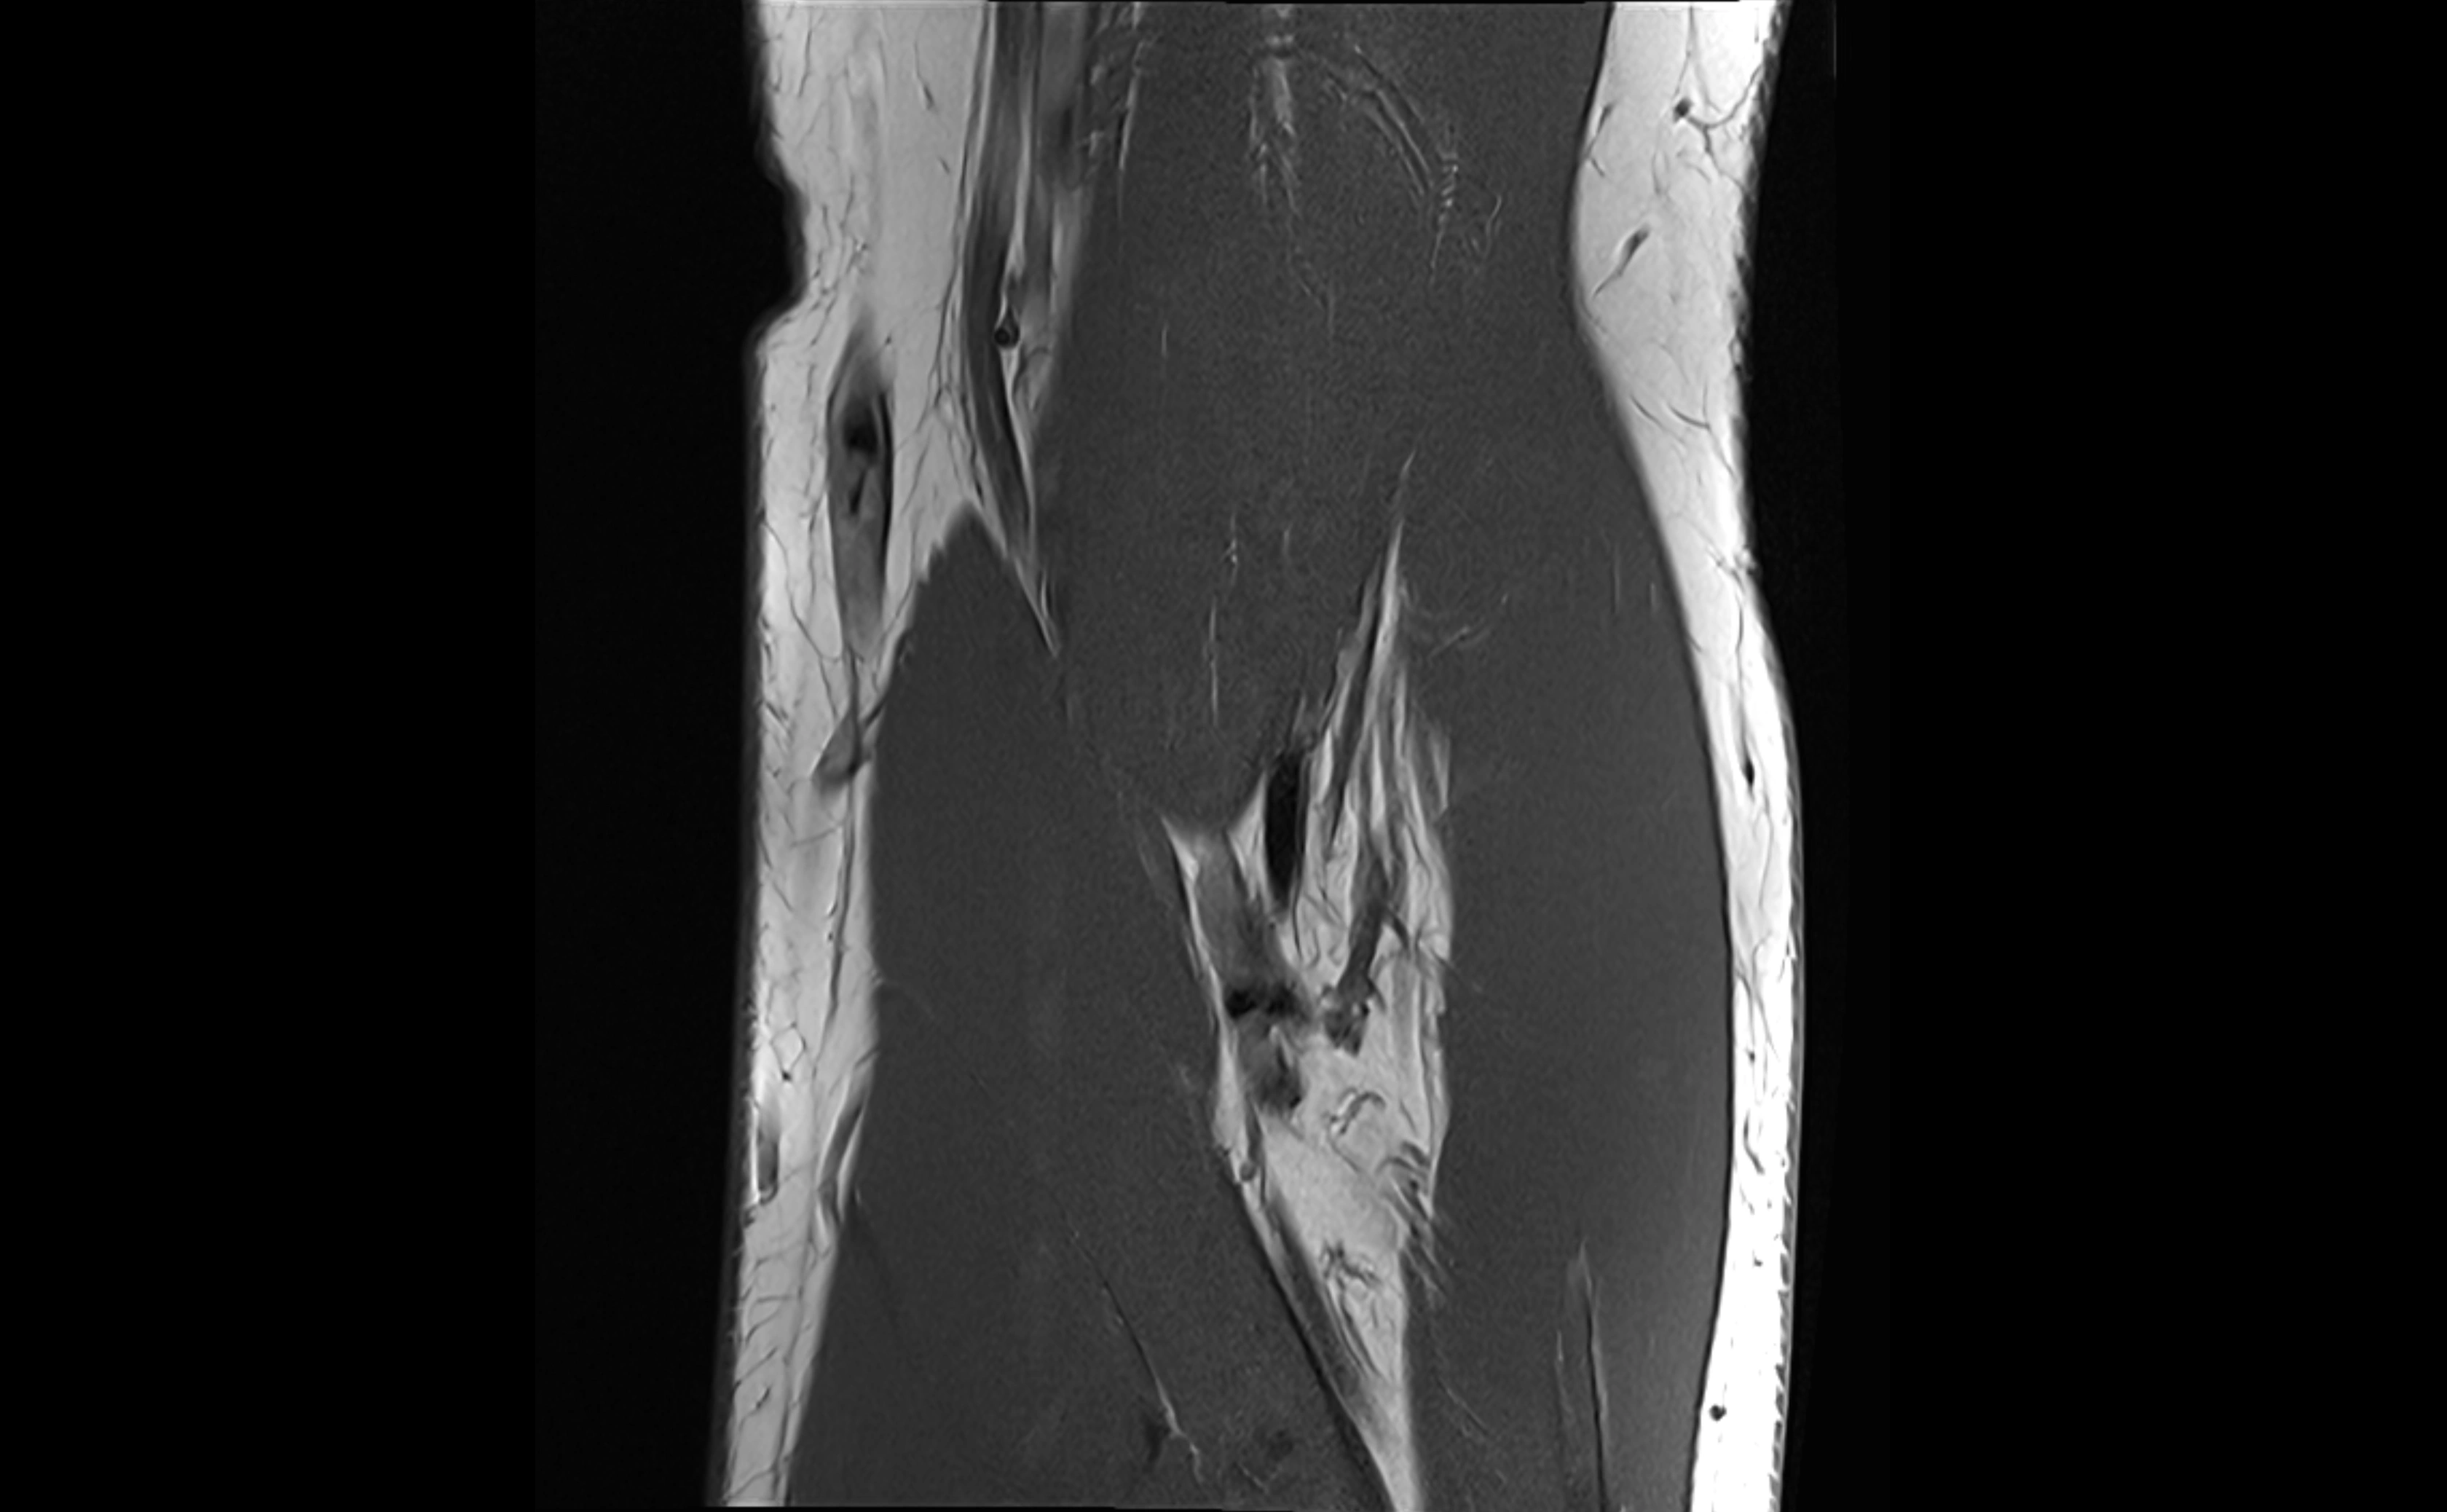

MRI images

image